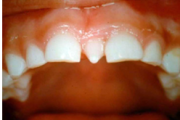

Normaalse jäävhammaskonna pilt küljelt ja eest vaadatuna.